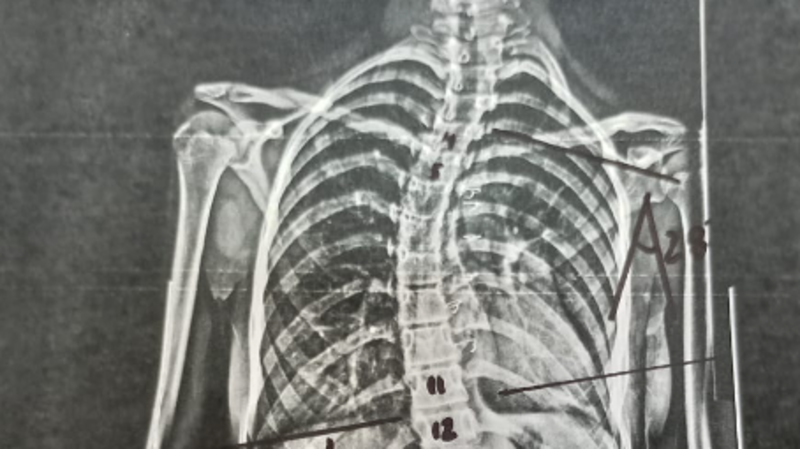

Ajude a Sofia 12 anos a comprar um Colete (3D) para escoliose Idiopática.

Devido ao possível agravamento da escoliose com crescimento da jovem, venho pedir seu apoio, qualquer valor que você puder, será de grande ajuda para o tratamento.